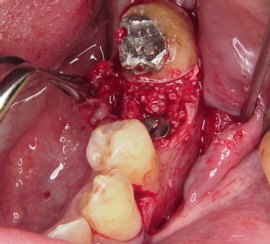

歯茎をめくると乳歯があります。

この下に永久歯が埋まっています。

抜歯した乳歯です。

抜歯後は多くの症例で

このような骨の裂開ができます。

インプラントを埋入して骨で裂開を塞ぎます。

歯茎をめくると乳歯があります。

この下に永久歯が埋まっています。

抜歯した乳歯です。

抜歯後は多くの症例で

このような骨の裂開ができます。

インプラントを埋入して骨で裂開を塞ぎます。